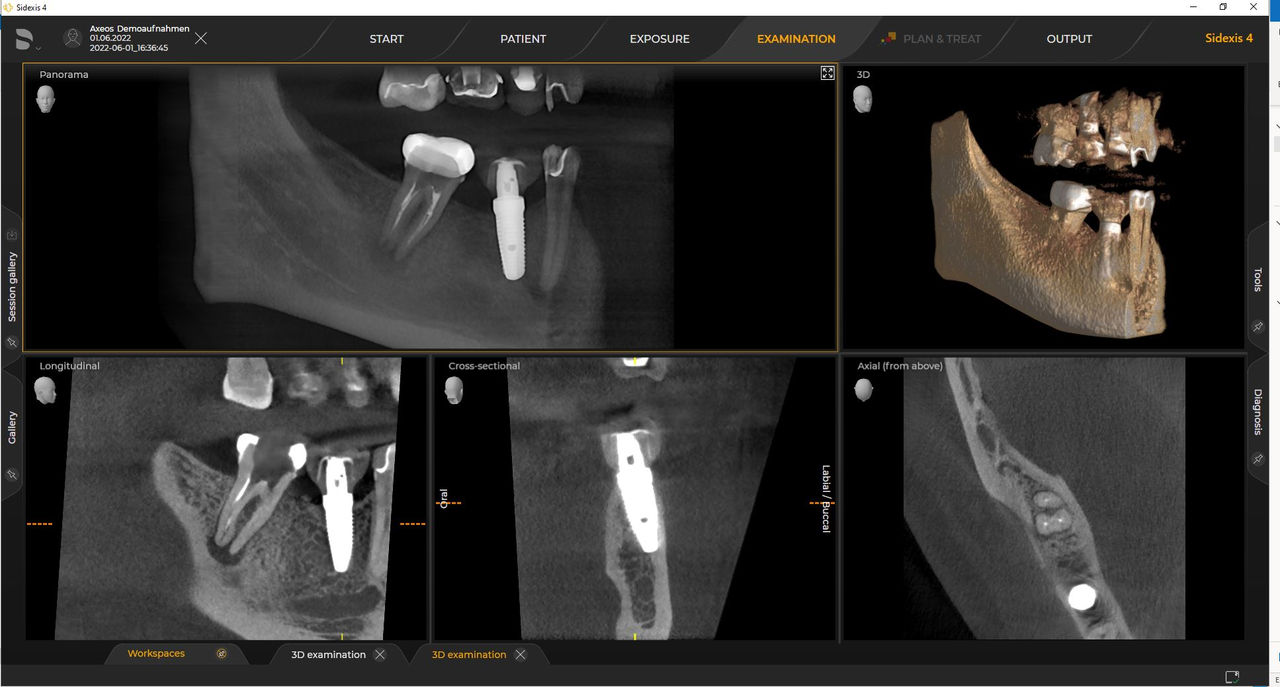

Axeos – the 2D/3D specialist system with a large volume and high image quality for practices with a broad treatment offering. Developed together with dentists and clinicians, Axeos provides the fullest range of functions out of all Dentsply Sirona extraoral X-ray devices. In addition to excellent image quality and tailor-made 3D volume sizes, the dental imaging device is fully optimised for enhanced patient comfort. Axeos not only provides quality in performance and comfort, but also with its award-winning design thanks to the integrated bite block accessory cabinet and ambient light.

Dentsply Sirona 3D units work exclusively with Sidexis 4. Nevertheless data migration from Sidexis XG to Sidexis 4 is very easy. Sidexis 4 allows for the full digital experience with the latest tools.